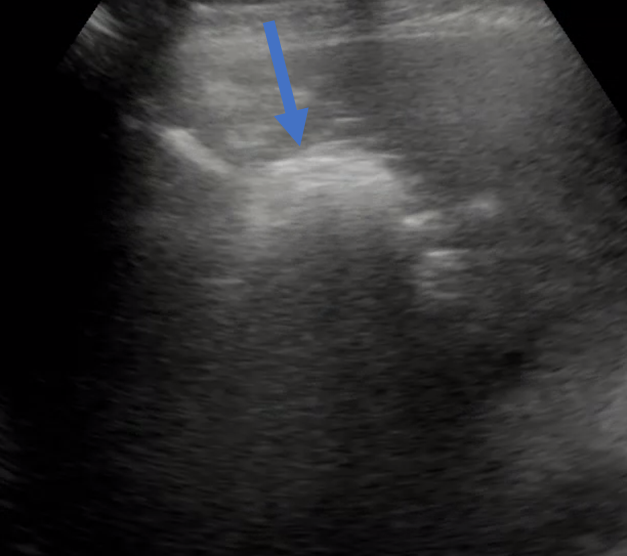

먼저, 초음파를 이용해서 목표로 하는 액체 저류(농양)이 어디서 잘 보이는지 확인합니다.

절개한 이후에는 초음파를 보면서 위에 제가 올린 Chiba needle 이라는 바늘로 목표한 병변을 찌릅니다.